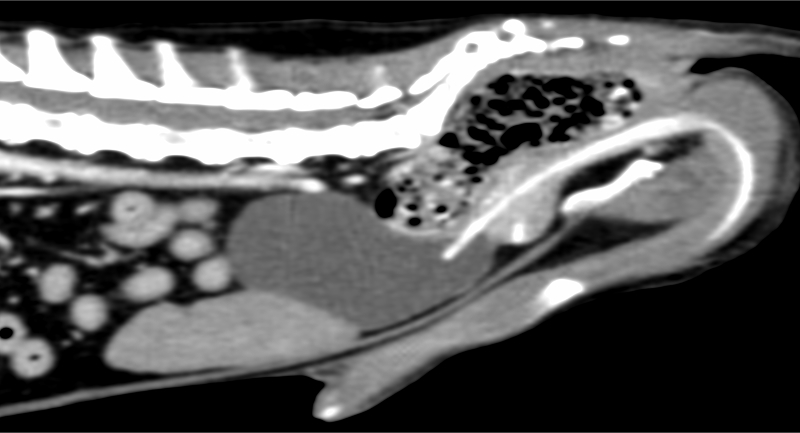

前立腺癌のCT検査画像。補助診断としてBRAF遺伝子検査が実施されました

犬の膀胱移行上皮癌や前立腺癌では、BRAF遺伝子変異検査を実施することがあります。膀胱移行上皮癌や前立腺癌では、BRAF遺伝子変異が高確率で検出されることが報告されています。